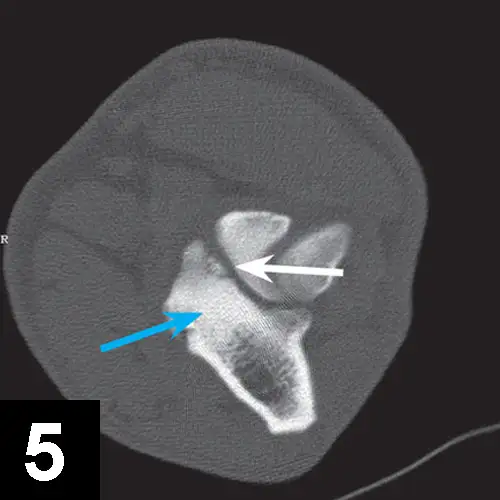

This pathology has a multifactorial etiology that affects the coxofemoral joint, most commonly in large-breed dogs (especially the German shepherd dog), but can also affect small-breed dogs and cats. Genetic and environmental factors can lead to joint laxity, which subsequently causes abnormal development of the acetabulum and femoral head, ultimately resulting in OA. Diagnosis in young patients is based on clinical signs (eg, difficulty in rising, swinging of the hindlimbs, pain, subluxation and laxity of the femoral head [Ortolani test]). Radiographic findings that confirm hip dysplasia are joint subluxation, incongruency, and early degenerative changes (Figure 1).

Figure 1. Ventrodorsal radiograph of the pelvis in a 12-month-old Labrador retriever with bunny-hopping and pain on extension of the hips. Bilateral coxofemoral subluxation and mild OA are evident.